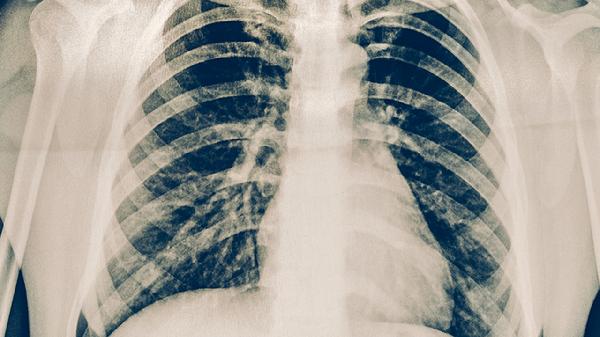

肺結核和原發(fā)性肺結核不一樣,原發(fā)性肺結核是肺結核的一種特殊類型。肺結核是由結核分枝桿菌引起的慢性傳染病,原發(fā)性肺結核特指初次感染結核桿菌后發(fā)生的肺部病變。

肺結核是一個廣泛的疾病概念,包含多種臨床類型,原發(fā)性肺結核屬于其中一種。原發(fā)性肺結核多見于兒童和青少年,通常表現為肺門淋巴結腫大和肺部原發(fā)病灶。這種類型的特點是患者首次接觸結核桿菌后,免疫系統(tǒng)尚未建立有效防御機制,導致局部淋巴結反應明顯。原發(fā)性肺結核的典型影像學表現為原發(fā)綜合征,包括肺部原發(fā)病灶、淋巴管炎和肺門淋巴結腫大三聯(lián)征。患者可能出現低熱、乏力、盜汗等結核中毒癥狀,部分兒童可能無明顯癥狀。

普通肺結核則包含多種表現形式,除原發(fā)性肺結核外,還包括繼發(fā)性肺結核、血行播散性肺結核、結核性胸膜炎等。繼發(fā)性肺結核是成人最常見的類型,多發(fā)生在曾經感染過結核桿菌的人群中,表現為肺部浸潤性病變或空洞形成。與原發(fā)性肺結核不同,繼發(fā)性肺結核患者由于存在部分免疫力,病變多局限于肺尖或上葉后段,較少出現明顯的淋巴結腫大。臨床癥狀相對明顯,常見咳嗽、咳痰、咯血等呼吸道癥狀。